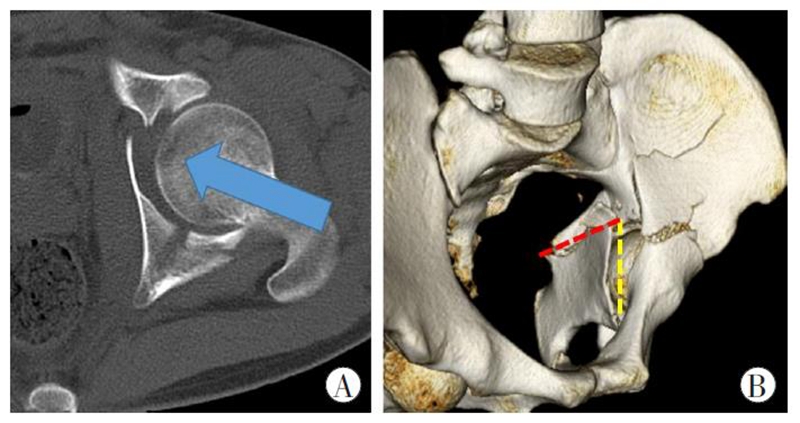

图2 四边体骨折致伤机制和形成条件

A.股骨头向前、向内的暴力撞击(蓝色箭头所示方向)是导致四边体骨折的主要致伤机制;B.垂直骨折线(黄色虚线)和横形骨折线(红色虚线)是四边体骨折形成的前提条件。